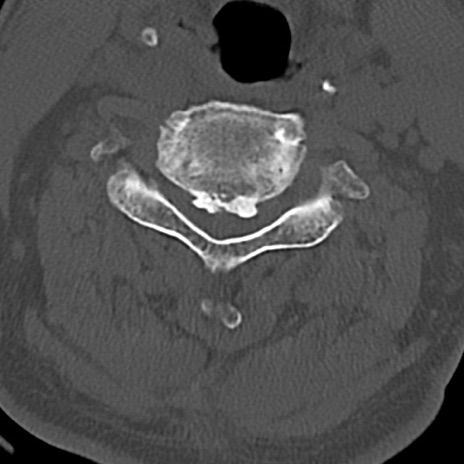

頚椎CT

横断像